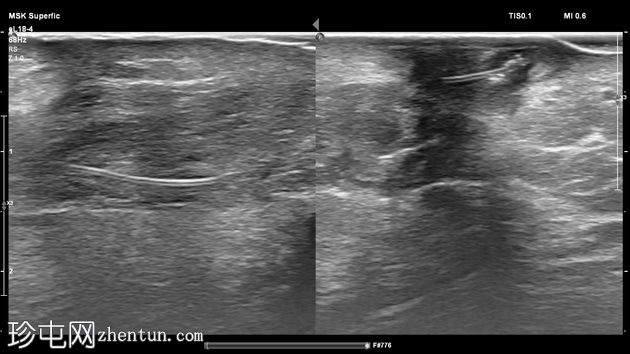

纵位

左足跟皮下组织内可见一管状高回声物质,呈串珠状,与手术缝线相符,周围环绕着低回声积液。与缝线相连的是一根细细的、呈轨道状的高回声合成单丝,它穿过跟腱呈弧形走行,该缝线为不可吸收缝线。